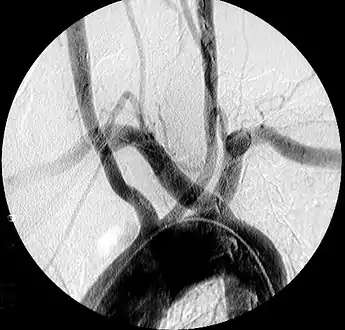

Aberrant subclavian artery on MR angiography.

Aberrant subclavian artery is a rare anatomical variant of the origin of the right or left subclavian artery. It is the most common congenital vascular anomaly of the aortic arch,[1] occurring in approximately 1% of individuals.[1][2][3]